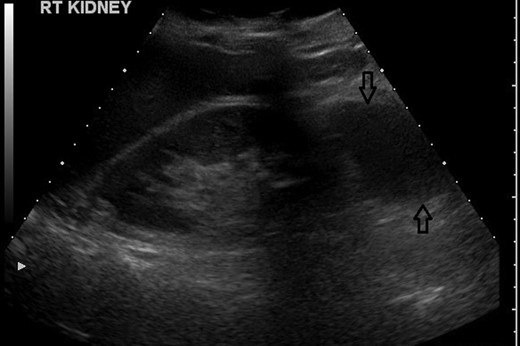

An urgent USS confirmed a staghorn calculus in the lower pole of her right kidney and an apparent 66 mm simple cyst was also identified adjacent to the lower pole of the kidney (Fig. 2). There was no hydronephrosis seen in either the kidney and the bladder appeared to be normal as well.

USS showing a suspected simple cyst on the lower pole of the right kidney.